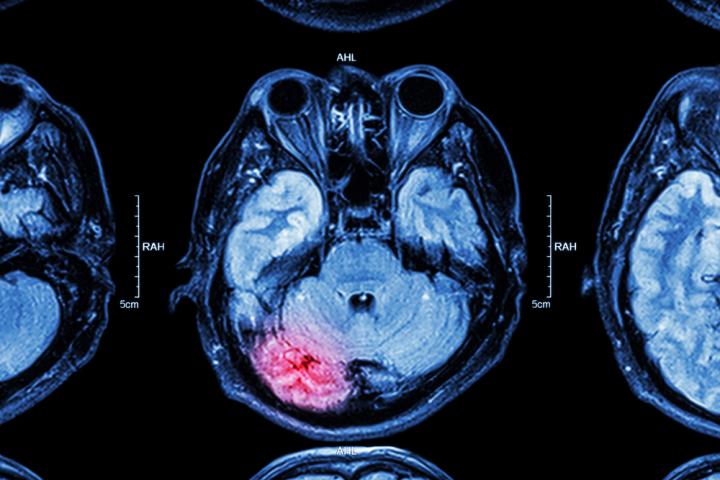

image: UTSA researchers removed new neurons that formed following a seizure in mice. The team then monitored seizure activity and observed that the treated mice experienced a 65% reduction in seizures compared to untreated mice.

Hsieh and her colleagues at The University of Texas at San Antonio systematically removed new neurons that formed during the eight weeks following a seizure in mice. The UTSA team then monitored seizure activity in the mice and observed that the treated mice experienced a 65 percent reduction in seizures compared to untreated mice. This effect required more than four weeks of continuous treatment.